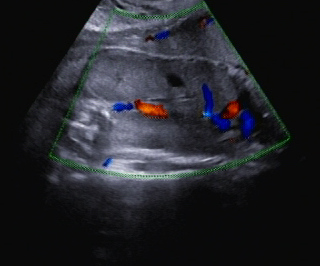

Im Abdomen war die Blase nicht gefüllt darstellbar (Abb. 4).